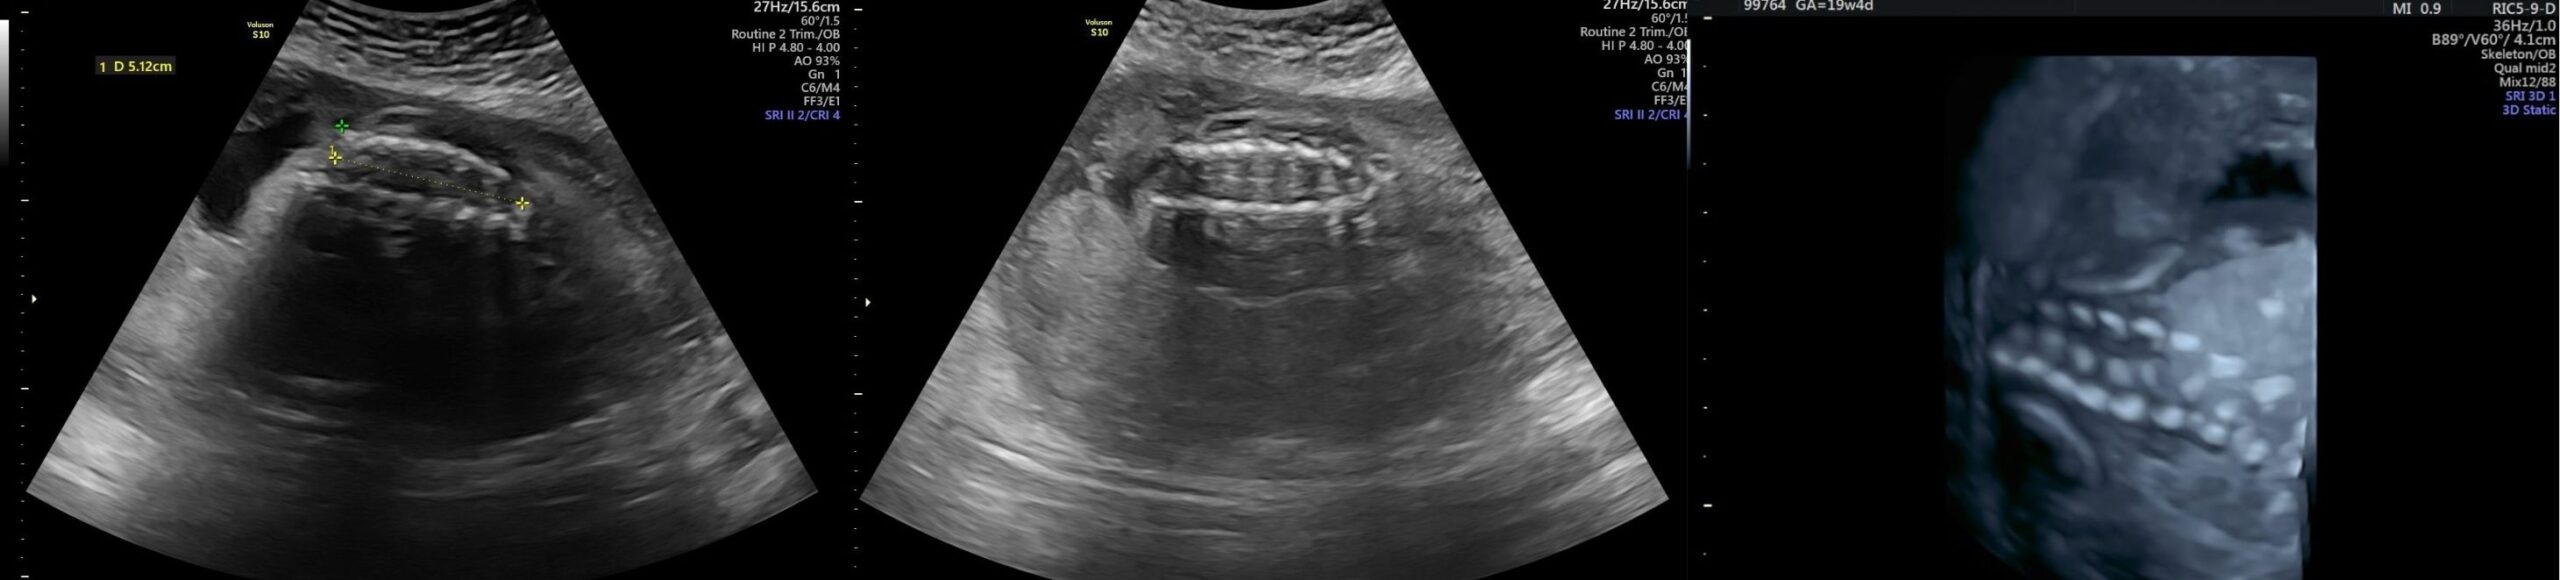

- Ultrassom Morfológico do 2º Trimestre

- Ultrassonografia em 3D/4D